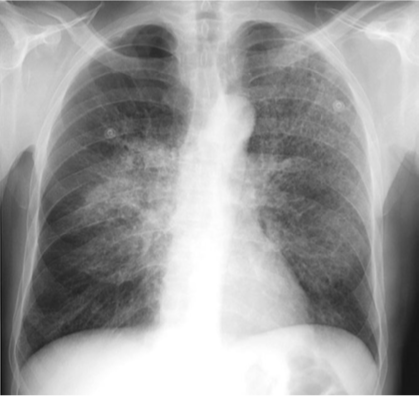

Pneumocystis carinii ( jiroveci) pneumonia (PCP).

There is bilateral, centrally- located interstitial lung disease that is primarily reticular in nature. Without the additional history that this patient had AIDS, this could be mistaken for pulmonary interstitial edema or for a chronic, fibrotic process such as sarcoidosis. There are, however, no pleural effusions present, as might be expected with pulmonary interstitial edema, and there is no evidence of hilar adenopathy, as might occur in sarcoidosis.